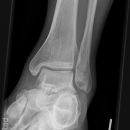

Totale Talusluxation

Nagel im Fuß